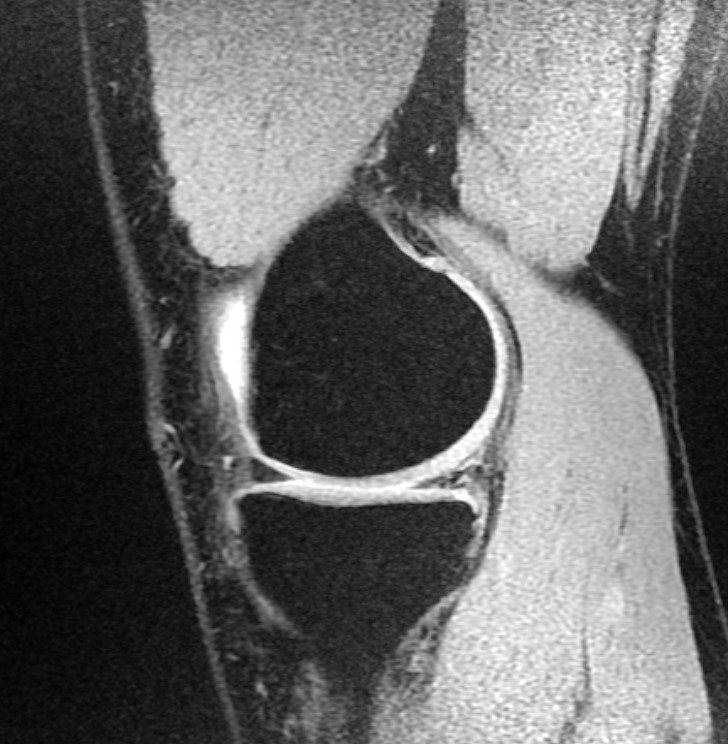

Η απεικονιστική εξέταση που ενδείκνυται για την διάγνωση των ρήξεων μηνίσκου είναι η Μαγνητική τομογραφία.

Ο ακτινολογικός έλεγχος δεν είναι απαραίτητος αφού οι μηνίσκοι δεν απεικονίζονται στην απλή ακτινογραφία.